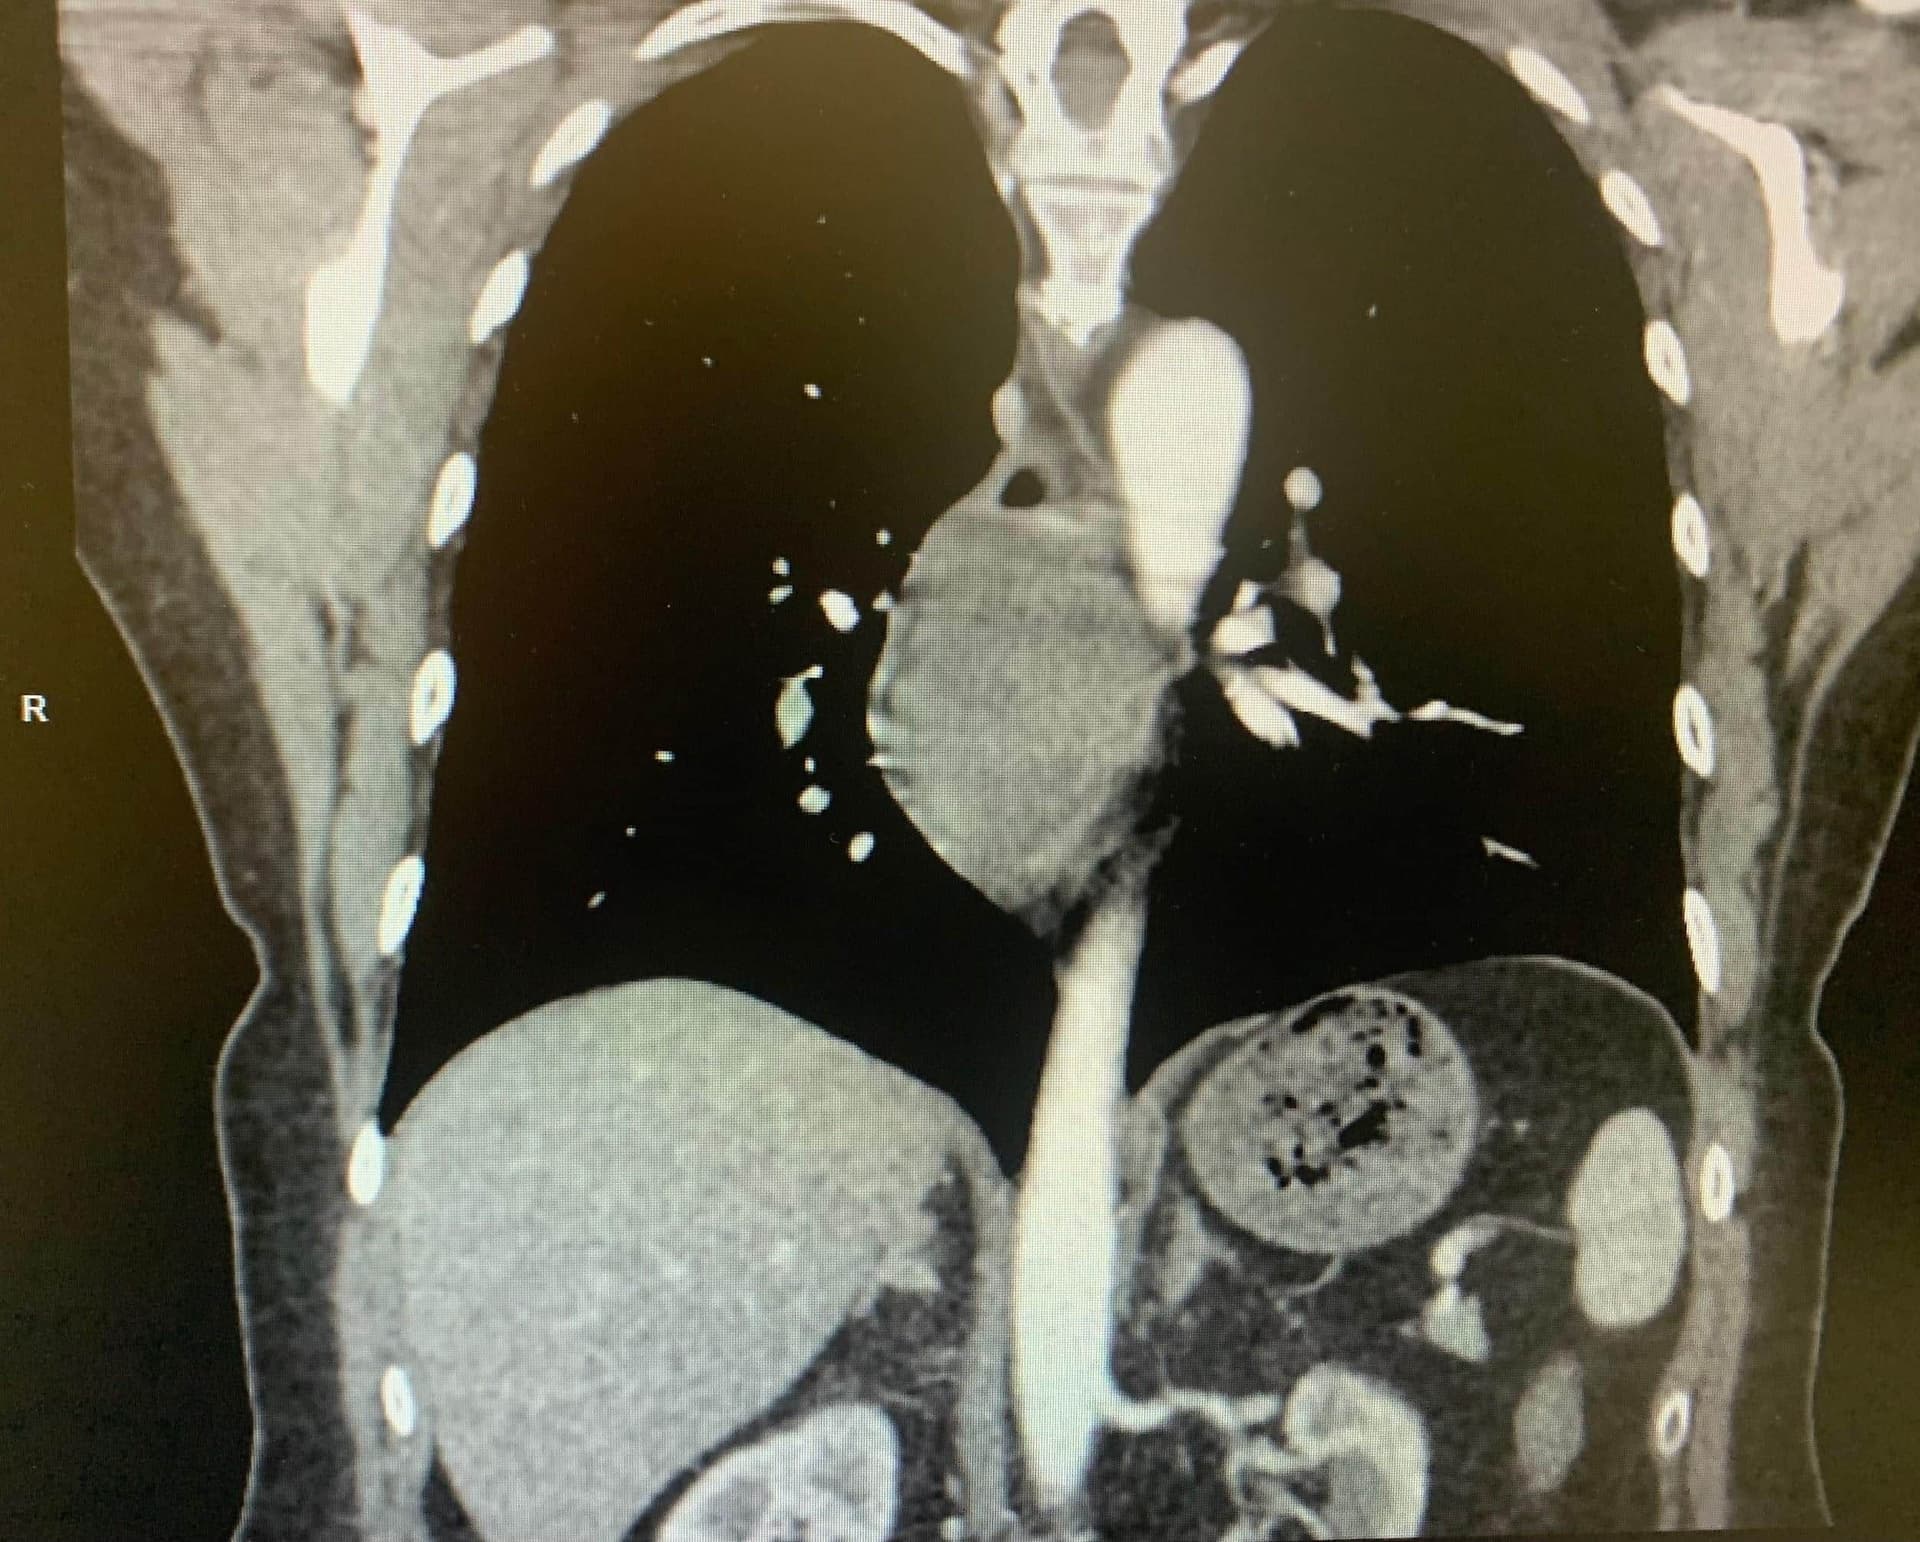

КТ з внутрішньовенним контрастуванням корисна для подальшого диференціювання утворення з іншими прилеглими структурами середостіння, а також визначення ступеня ураження довжини стравоходу. На КТ пухлина часто описується як округле, ексцентричне, рівномірно щільне, іноді долькове, гладке утворення навколо стінки стравоходу (зобр. 3).[3,7]

КТ-візуалізація може бути корисною для визначення проведення подальших діагностичних або хірургічних методів, якщо це показано.

Зображення 3. КТ з внутрішньовенним контрастуванням показує циркулярне, ексцентричне, рівномірно щільне, іноді долькове, гладке утворення навколо стінки стравоходу.